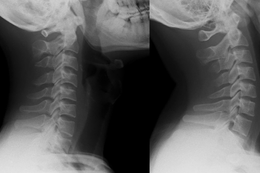

Bệnh nhi B.G.H. (15 tuổi, xã Lai Đồng, Phú Thọ) là một ví dụ điển hình. Ban đầu, em chỉ cảm thấy tê cứng nhẹ vùng lưng. Theo thời gian, các cơn đau tăng dần, nhất là khi bệnh nhân vận động mạnh. Đến khi cơn đau vượt quá sức chịu đựng, gia đình đưa em đi khám tại Bệnh viện Đa khoa tỉnh Phú Thọ và bất ngờ khi nhận kết luận thoái hóa đốt sống kèm thoát vị đĩa đệm nặng.

BSCKII Phan Thanh Hải, Phó Trưởng khoa Ngoại Thần kinh, Bệnh viện Đa khoa tỉnh Phú Thọ cho biết, số bệnh nhân trẻ thoát vị đĩa đệm đang gia tăng rõ rệt. Theo đó, có những bệnh nhân mới 15 tuổi đã bị thoát vị nặng, phải điều trị dài ngày.

Một nam nhân viên văn phòng 26 tuổi đã phải tìm đến bác sĩ vì tình trạng đau cổ vai gáy kéo dài. Kết quả chiếu chụp ghi nhận cột sống của bệnh nhân “thẳng như cây gậy”.